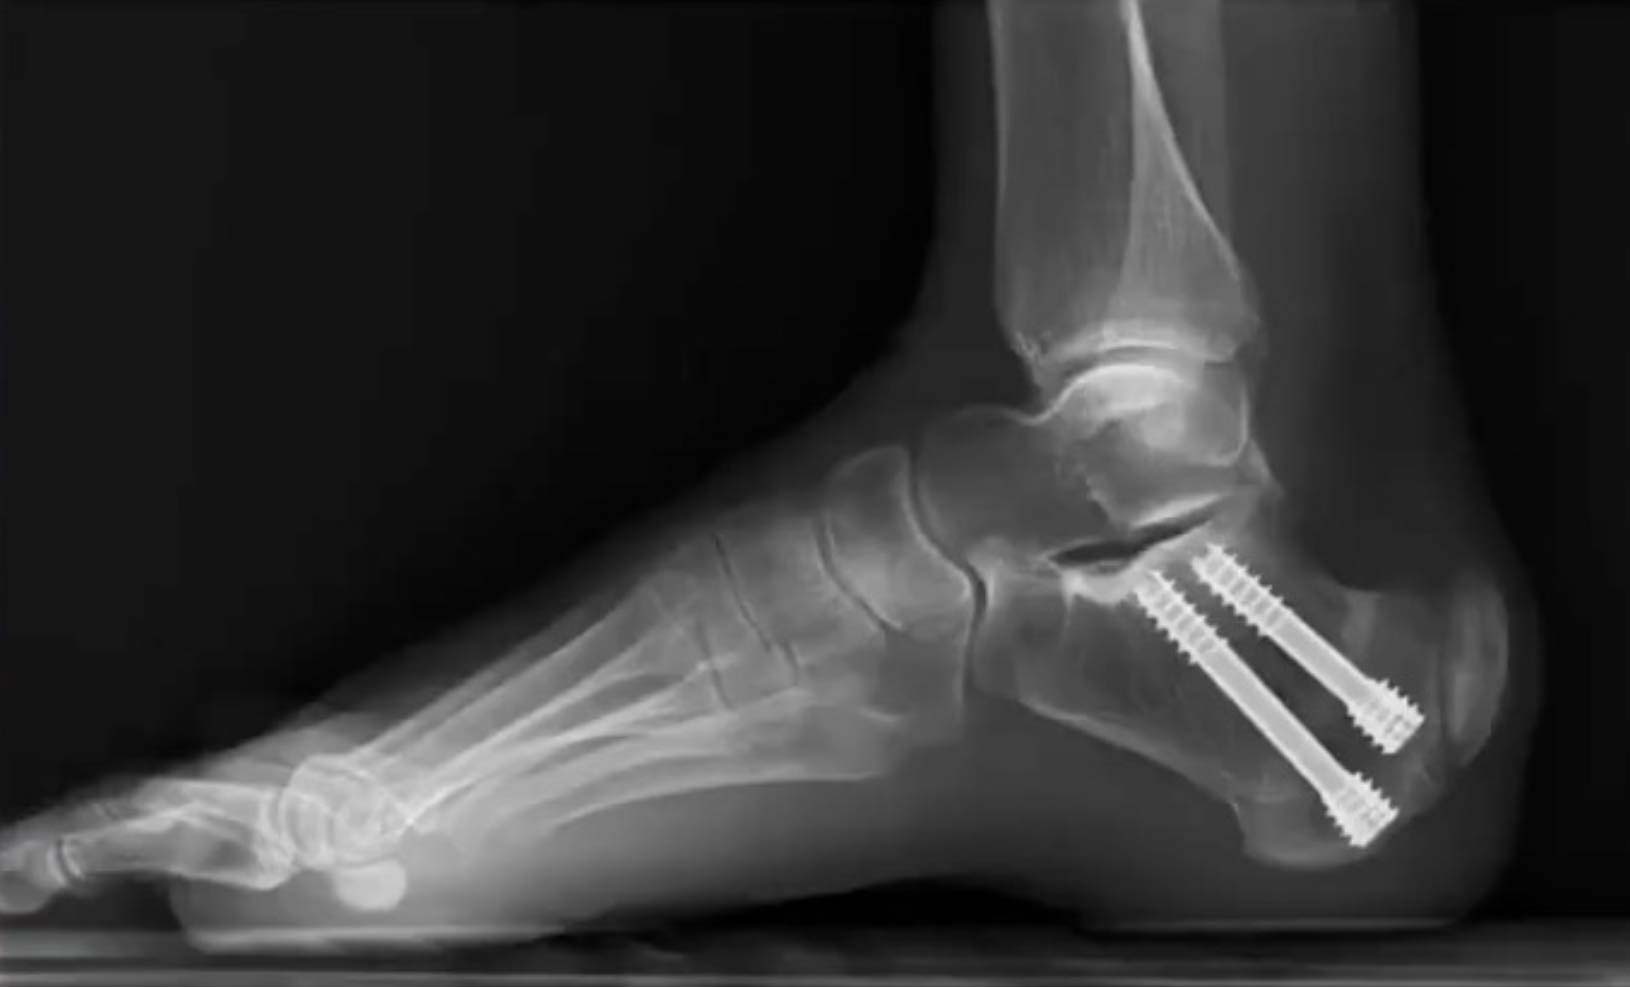

The core premise of the Zadek procedure is to change the biomechanical environment to allow the body to heal itself. By making a small cut in the heel bone and removing a wedge, the surgeon alters the angle by which the Achilles tendon inserts on the calcaneus. This decompresses the entire area, alleviating the tension and strain that caused the inflammation and pain in the first place, while allowing the tendon to heal naturally.

The procedure was first developed and published by Dr. Isadore Zadek in 1939. However, this original technique involved a large, open incision on the side of the heel. While the biomechanical concept was effective and patients had resolution of their posterior heel pain, this procedure was largely abandoned due to high rates of wound complications associated with such a significant incision in an area with delicate blood supply.

Today, modern MIS techniques have allowed surgeons to bring this effective concept back from the history books. Using specialized tools like a Shannon burr through incisions barely a few millimeters long, surgeons can now perform the osteotomy and achieve the same powerful biomechanical correction without the historical drawbacks of an open approach.